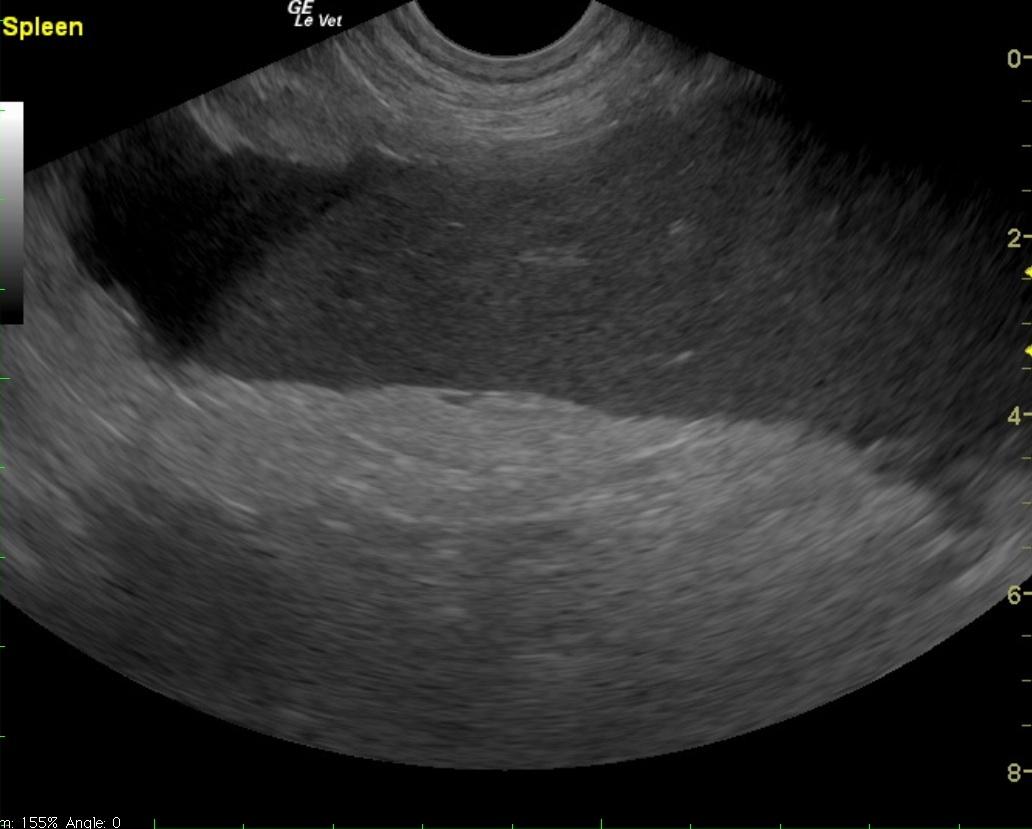

A 6-year-old intact male English Bulldog was presented for 2-3 days of intermittent vomiting and lethargy. Physical exam found the patient to be tachycardic with pale mucous membranes and a palpable mass in the abdomen. Serum biochemistry revealed elevated alkaline phosphatase, hypernatremia, and mild hypochloremia. On CBC, a decreased HCT in conjunction with a high MCV was noted, in addition to a neutrophilia, monocytosis and thrombocytopenia. No abnormalities were noted on thoracic radiographs. Abdominal radiographic findings revealed a loss of contrast in the cranial abdomen, with the possibility of a splenic mass. Radiographic Interpretation showed marked splenomegaly strongly suspected to be secondary to torsion, although accompanying infiltrative or neoplastic pathology could not be ruled out. The small volume of peritoneal effusion and inflammation was likely secondary to the splenic pathology. Thoracic radiographs showed mild microcardia and under perfused pulmonary vasculature in support of hypovolemia. Atypical intrathoracic fat distribution was considered to be incidental in this dog. This dog had multiple hemivertebrae.